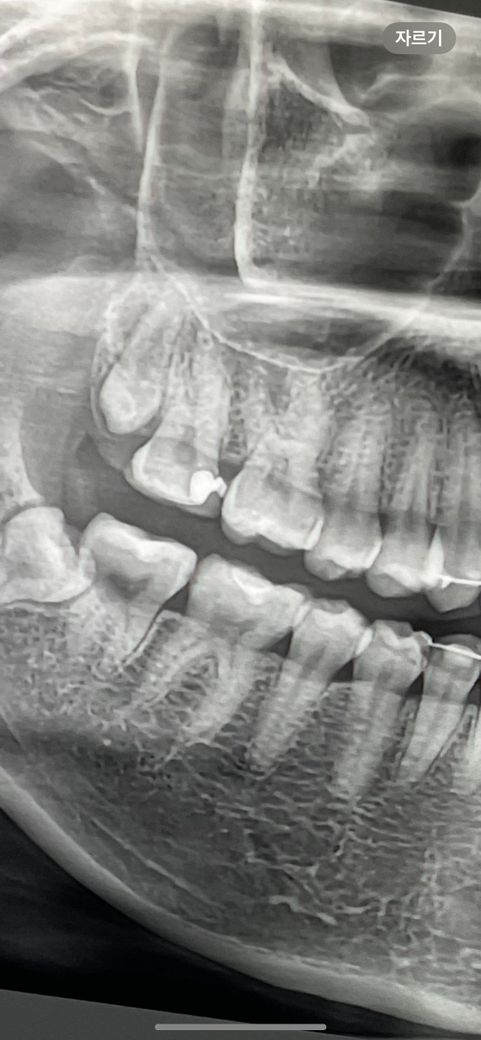

가장 최근에 찍었던 (3개월 전) 찍었던 엑스레이도 함께 첨부합니다 ㅠㅠ

• 2번 째 사진

사랑니 때문에 염증이 생긴 것으로 보입니다. 사랑니 염증이 사랑니 바로앞 어금니쪽으로 퍼진 것입니다. 사랑니가 잇몸에 매복된 상태입니다. 사랑니를 뽑아야만 치료가 됩니다.

저건 2차원 사진이니 보이는 것보다 옆 어금니와 더 겹쳐있을 수 있습니다 아무래도 사랑니로 인한 문제로 보입니다